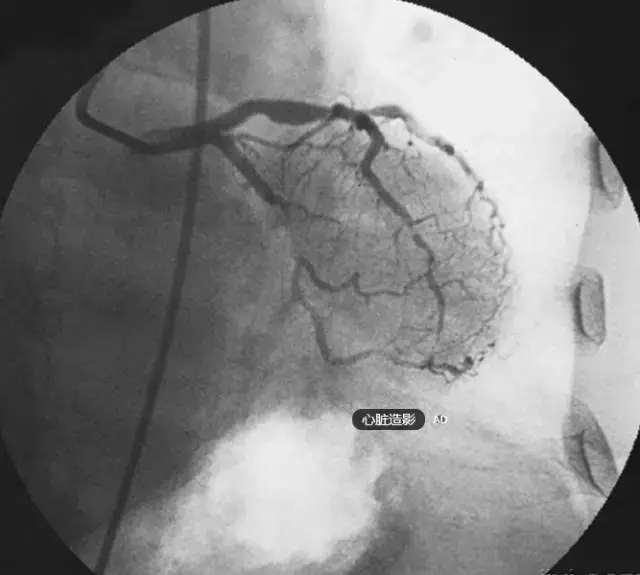

冠狀動脈造影簡稱冠脈造影,是使冠狀動脈在X線下顯影的方法。

冠狀動脈是供應(yīng)心肌血液的血管,分為左、右冠狀動脈,分別直接開口于主動脈根部的左、右主動脈竇內(nèi),由此開始向心臟表面延伸并不斷分支進入心臟。

由于血液與血液壁是同樣不透光的,且與心臟重疊,所以血管腔內(nèi)發(fā)生有粥樣斑塊或狹窄時,在普通X光下是無法看出的,只有通過血管造影才能發(fā)現(xiàn)這些病變。

根據(jù)血管受阻的程度不同,冠心病的臨床表現(xiàn)有心絞痛、心肌梗死、心律失常、無癥狀性心肌缺血、甚至猝死等。冠狀動脈造影不僅可以確定冠狀動脈是否存在阻塞以及阻塞的嚴重程度,還可以為下一步的治療方案提供依據(jù)。